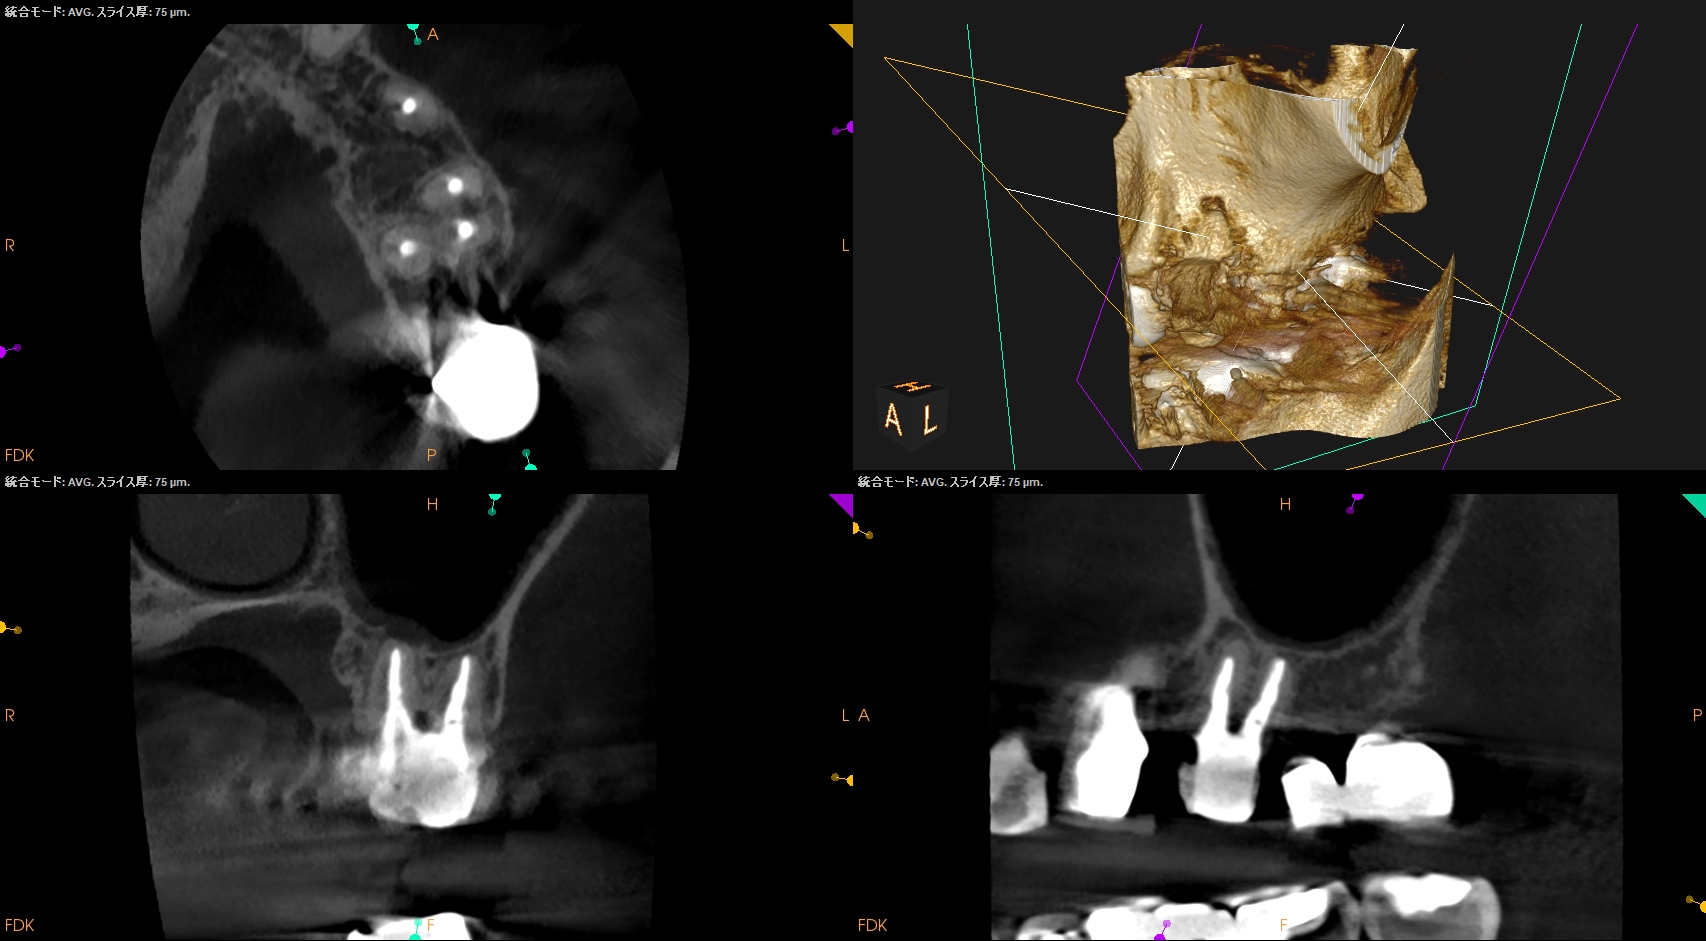

#3,14,16 Re-RCT 1yr recall(2025.10.20)

#3

MB

DB

P

#14

#16

初診時+治療直後と比較した。

劇的に病気が治癒している。

特に#16は凄まじい。

超音波洗浄しかできなかったのに根尖病変が治癒しているのだ。

免疫力が非常に強い患者さんなのだろう。